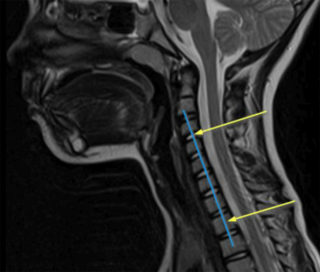

Для оценки состояния плоской спины стоит обратиться к ортопеду, травматологу или неврологу. Врач проведет осмотр, опрос и назначит дополнительные обследования. В первую очередь проводят рентгенографию позвоночника. Снимок, сделанный в боковой проекции, позволяет определить сглаживание естественных изгибов и компенсацию излишними прогибами. Если заболевание находится в запущенной форме, могут назначить УЗИ, КТ или МРТ. Эти методики позволяют оценить состояние не только костей, но и мышц, сосудов, нервов, суставов. Детальная диагностика поможет определить, насколько подверглись нарушениям смежные системы организма.

Точно определить, что шейный лордоз выпрямлен, может только хирург, ортопед или травматолог. Реже за диагностикой обращаются к терапевту. Назначают такие методы обследования:

- рентген и дискография;

- МРТ и КТ в тяжелых случаях при наличии подозрений на сопутствующие нарушения;